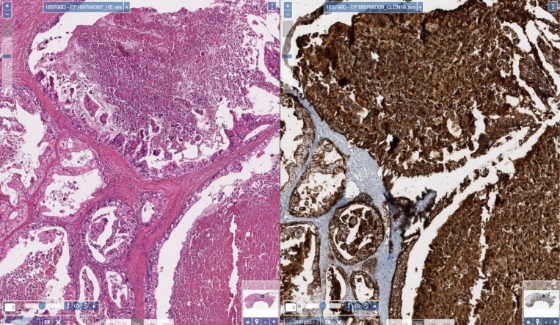

Comparación de la tinción con H&E e IHQ de la necrosis de tumor gástrico (aumento 10x)

Diversos estudios han evaluado tanto la tinción de las membranas como el porcentaje de células tumorales teñidas para la expresión de CLDN18.21,2.

En tumores G/UGE, la CLDN18.2 se reporta como el porcentaje de células teñidas con una intensidad de tinción de la membrana de moderada a intensa1.

• Las laminillas de tejido que presentan células tumorales pueden mostrar distintos niveles de intensidad de tinción de CLDN18 de membrana, que van desde ausencia de tinción a tinción intensa (0 a 3+).

• Muchos estudios han incluido para la puntuación de la CLDN18 exclusivamente los porcentajes de células tumorales que mostraban tinción de membrana de moderada a intensa (2+/3+).

• Durante la interpretación debe tenerse en cuenta la necrosis tumoral.